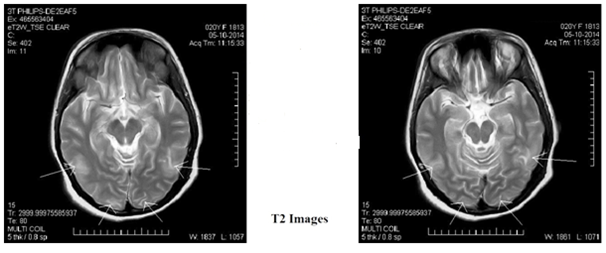

A 20year old female patient presented to the emergency department with history of bilateral loss of vision since three days. She complained of painless non progressive complete loss of vision, which was sudden in onset in both the eyes immediately after undergoing lower segment caesarian section under spinal anesthesia for pre-eclampsia in another center. There was no history of nausea, vomiting or convulsions. On examination, her visual acuity was perception of light with inaccurate projection of rays bilaterally. Pupils were 3mm in size, normally reactive and afferent papillary defect was absent. Anterior segment examination was unremarkable. No abnormality was detected on fundus examination. Her neurological examination was also within normal limits. Magnetic Resonance Imaging (MRI) T2 and Fluid-Attenuated Inversion Recovery (FLAIR) sequences showed bilateral hyper-intensities primarily located in the cortex and adjacent sub-cortex of occipital and temporal lobes (Figure 1) (Figure 2). Blood pressure was 142/96mmHg on presentation. Other systemic findings including central nervous system examination was within normal limits.

Figure 1 Bilateral hyperintensities primarily located in the cortex and adjacent sub-context of occipital and temporal lobes.

Figure 2 Bilateral hyperintensities primarily located in the cortex and adjacent sub cortex of occipital and temporal lobes.

MRI typically demonstrates bilateral symmetrical hyper intensities in the parieto-occipital regions on T2-weighted and FLAIR sequence images. Occipital lobe is commonly involved in PRES but spares the calcarine and paramedian occipital lobe. This along with major involvement of the white matter is a distinguishing feature from bilateral posterior cerebral artery territory infarction. Our MRI findings correlated with the findings of Karuppannasamy D et al.,12 As systemic blood pressure rises, the brain’s autoregulatory capability fails and it results in hyperperfusion via increased cerebral blood flow and resulting edema. Judicious control of hypertension has been found to be the primary treatment along with supportive treatment to lower the intracerebral pressure.4 Our patient recovered full vision of 6/6 within 1week of treatment (Table 1) and was doing well on follow up at one month and three months. Her MRI did not show any lesions on follow up visits.